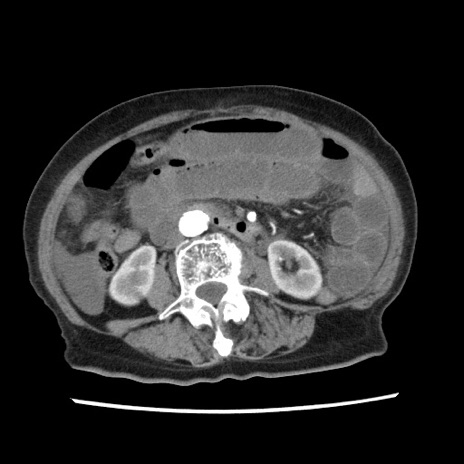

症例1(横断像)

【症例】80歳代女性

【主訴】腹痛

【現病歴】8時間前から腹痛あり来院。

【既往歴】糖尿病、脂質異常症、子宮体癌にて子宮全摘術

【身体所見】意識清明・会話良好だが腹痛で苦悶様、全腹部にわたって反跳痛と圧痛あり

【データ】WBC 13600、CRP 0.14、LDH 224、CK 90